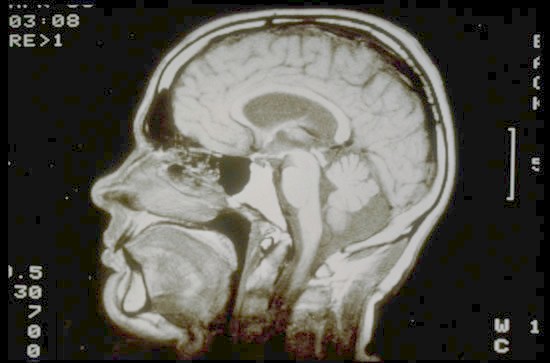

On Mr Smith’s screen a schematic showed Mr Lumsden’s brain.

The ‘organic data-file’ showed as a small green splodge about

the size of a pea.

“As small as that?” Clyde asked.